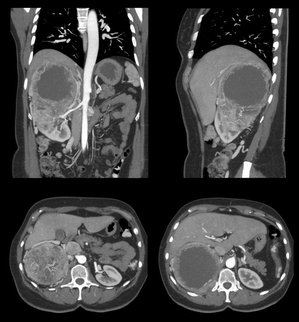

Die Computertomographie (CT) ist ein Röntgenverfahren. Die modernen Computertomographen sind in der Lage, mehrere Schichten des Körpers gleichzeitig zu untersuchen und die Bilder in Sekunden zu berechnen. Zugleich lassen sich Bilder in 3D berechnen, womit neue Bildeindrücke gegeben sind.

Die CT bietet in allen Bereichen ihrer Anwendung im Vergleich zur herkömmlichen Röntgenaufnahme eine erheblich höhere Aussagekraft. Dabei muss der höhere diagnostische Zugewinn mit einer höheren Strahlenexposition erkauft werden. Durch die moderne Technik wird bei dem Gerät nur die notwendige Menge an Röntgenstrahlung zur Erzeugung eines aussagekräftigen Bildes verwendet. Einige Untersuchungen können mit erheblich reduzierter Dosis angefertigt werden, zum Beispiel CT der Nasennebenhöhlen. Die gemessenen Dosiswerte werden protokolliert.

- alle Körperregionen einschließlich mehrdimensionaler Rekonstruktionen